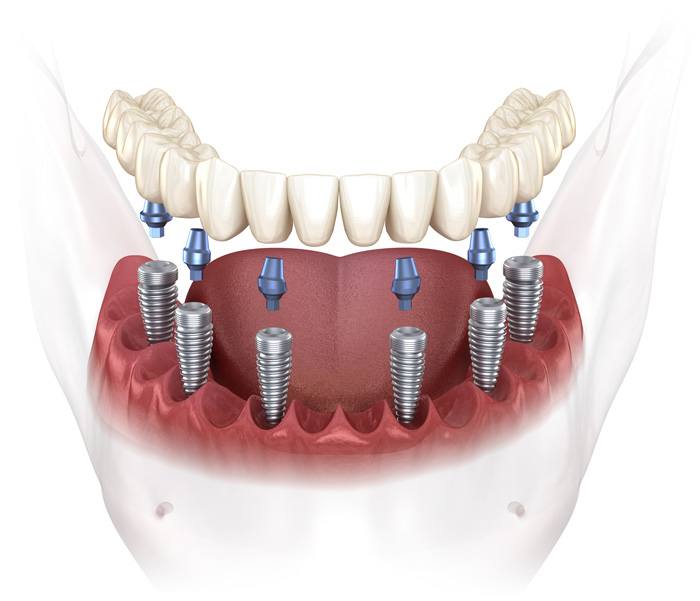

What are dental implants?

Learn how millions of Americans are replacing their teeth for life!

Patients no longer have to deal with low-quality temporary solutions like dentures, bridges, or partials. Dental implants are the new leading standard in tooth replacement options. They act and feel just like real teeth with an average lifespan of 20+ years.

Most traditional replacement solutions - like bridges or dentures - need to be replaced every 7 to 10 years resulting in hundreds of wasted dollars. Implants offer a long term solution for patients who want the best quality of life possible.

So, how do they work?

Every single dental implant consists of three parts - the implant, the abutment, & the crown. The implant is made of medical grade titanium. This part is surgically placed into the patient’s jaw bone and left to heal for 4-6 months afterwards.

This implant piece acts as the foundation for the rest of the tooth. Once the bone around the site has healed, the abutment and crown are placed on top of the implant. The end result is a beautiful, natural-looking new tooth!

Few people will ever be able to tell the difference between your implants and your real teeth.

What are dental implants?

Learn how millions of Americans are replacing their teeth for life!

Patients no longer have to deal with low-quality temporary solutions like dentures, bridges, or partials. Dental implants are the new leading standard in tooth replacement options. They act and feel just like real teeth with an average lifespan of 20+ years.

Most traditional replacement solutions - like bridges or dentures - need to be replaced every 7 to 10 years resulting in hundreds of wasted dollars. Implants offer a long term solution for patients who want the best quality of life possible.

So, how do they work?

Every single dental implant consists of three parts - the implant, the abutment, & the crown. The implant is made of medical grade titanium. This part is surgically placed into the patient’s jaw bone and left to heal for 4-6 months afterwards.

This implant piece acts as the foundation for the rest of the tooth. Once the bone around the site has healed, the abutment and crown are placed on top of the implant. The end result is a beautiful, natural-looking new tooth!

Few people will ever be able to tell the difference between your implants and your real teeth.